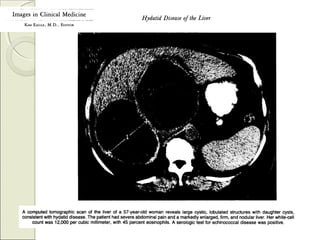

* TAC:* TAC: Infección presente -

pasada

* TAC:* TAC:Infección presente - pasada